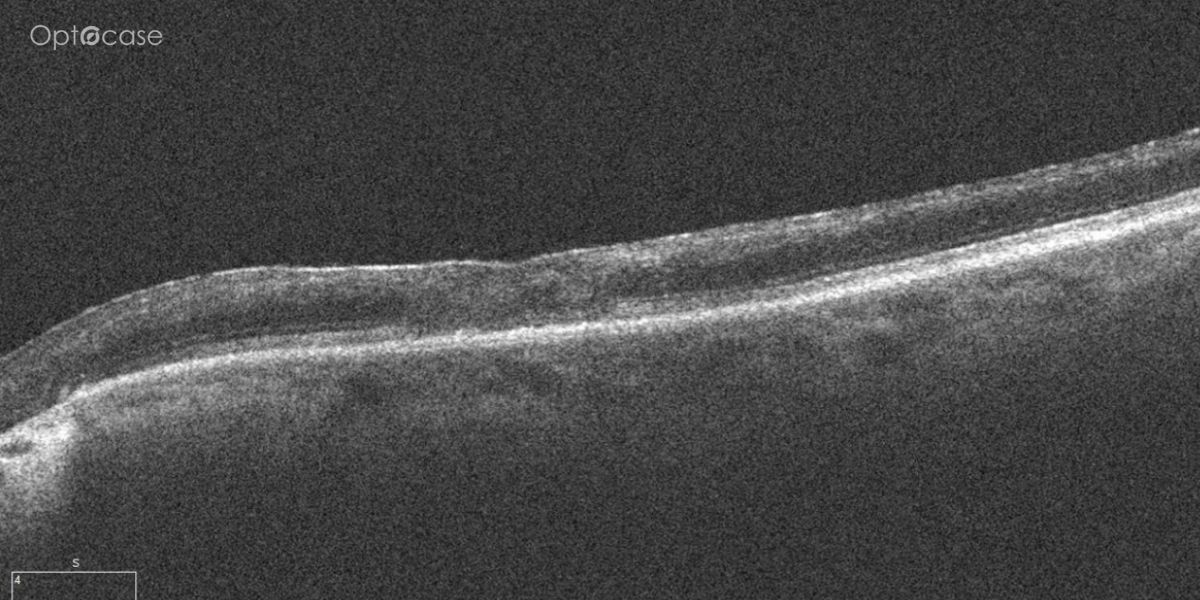

Here there is loss of the regular macular depression. There is a bright line present on the surface of the retina. In addition, there is separation of the retinal layers in the inner retina.

The patient was diagnosed with a schisis secondary to an epiretinal membrane. This complication is seen in over 50% of ERMs (video).